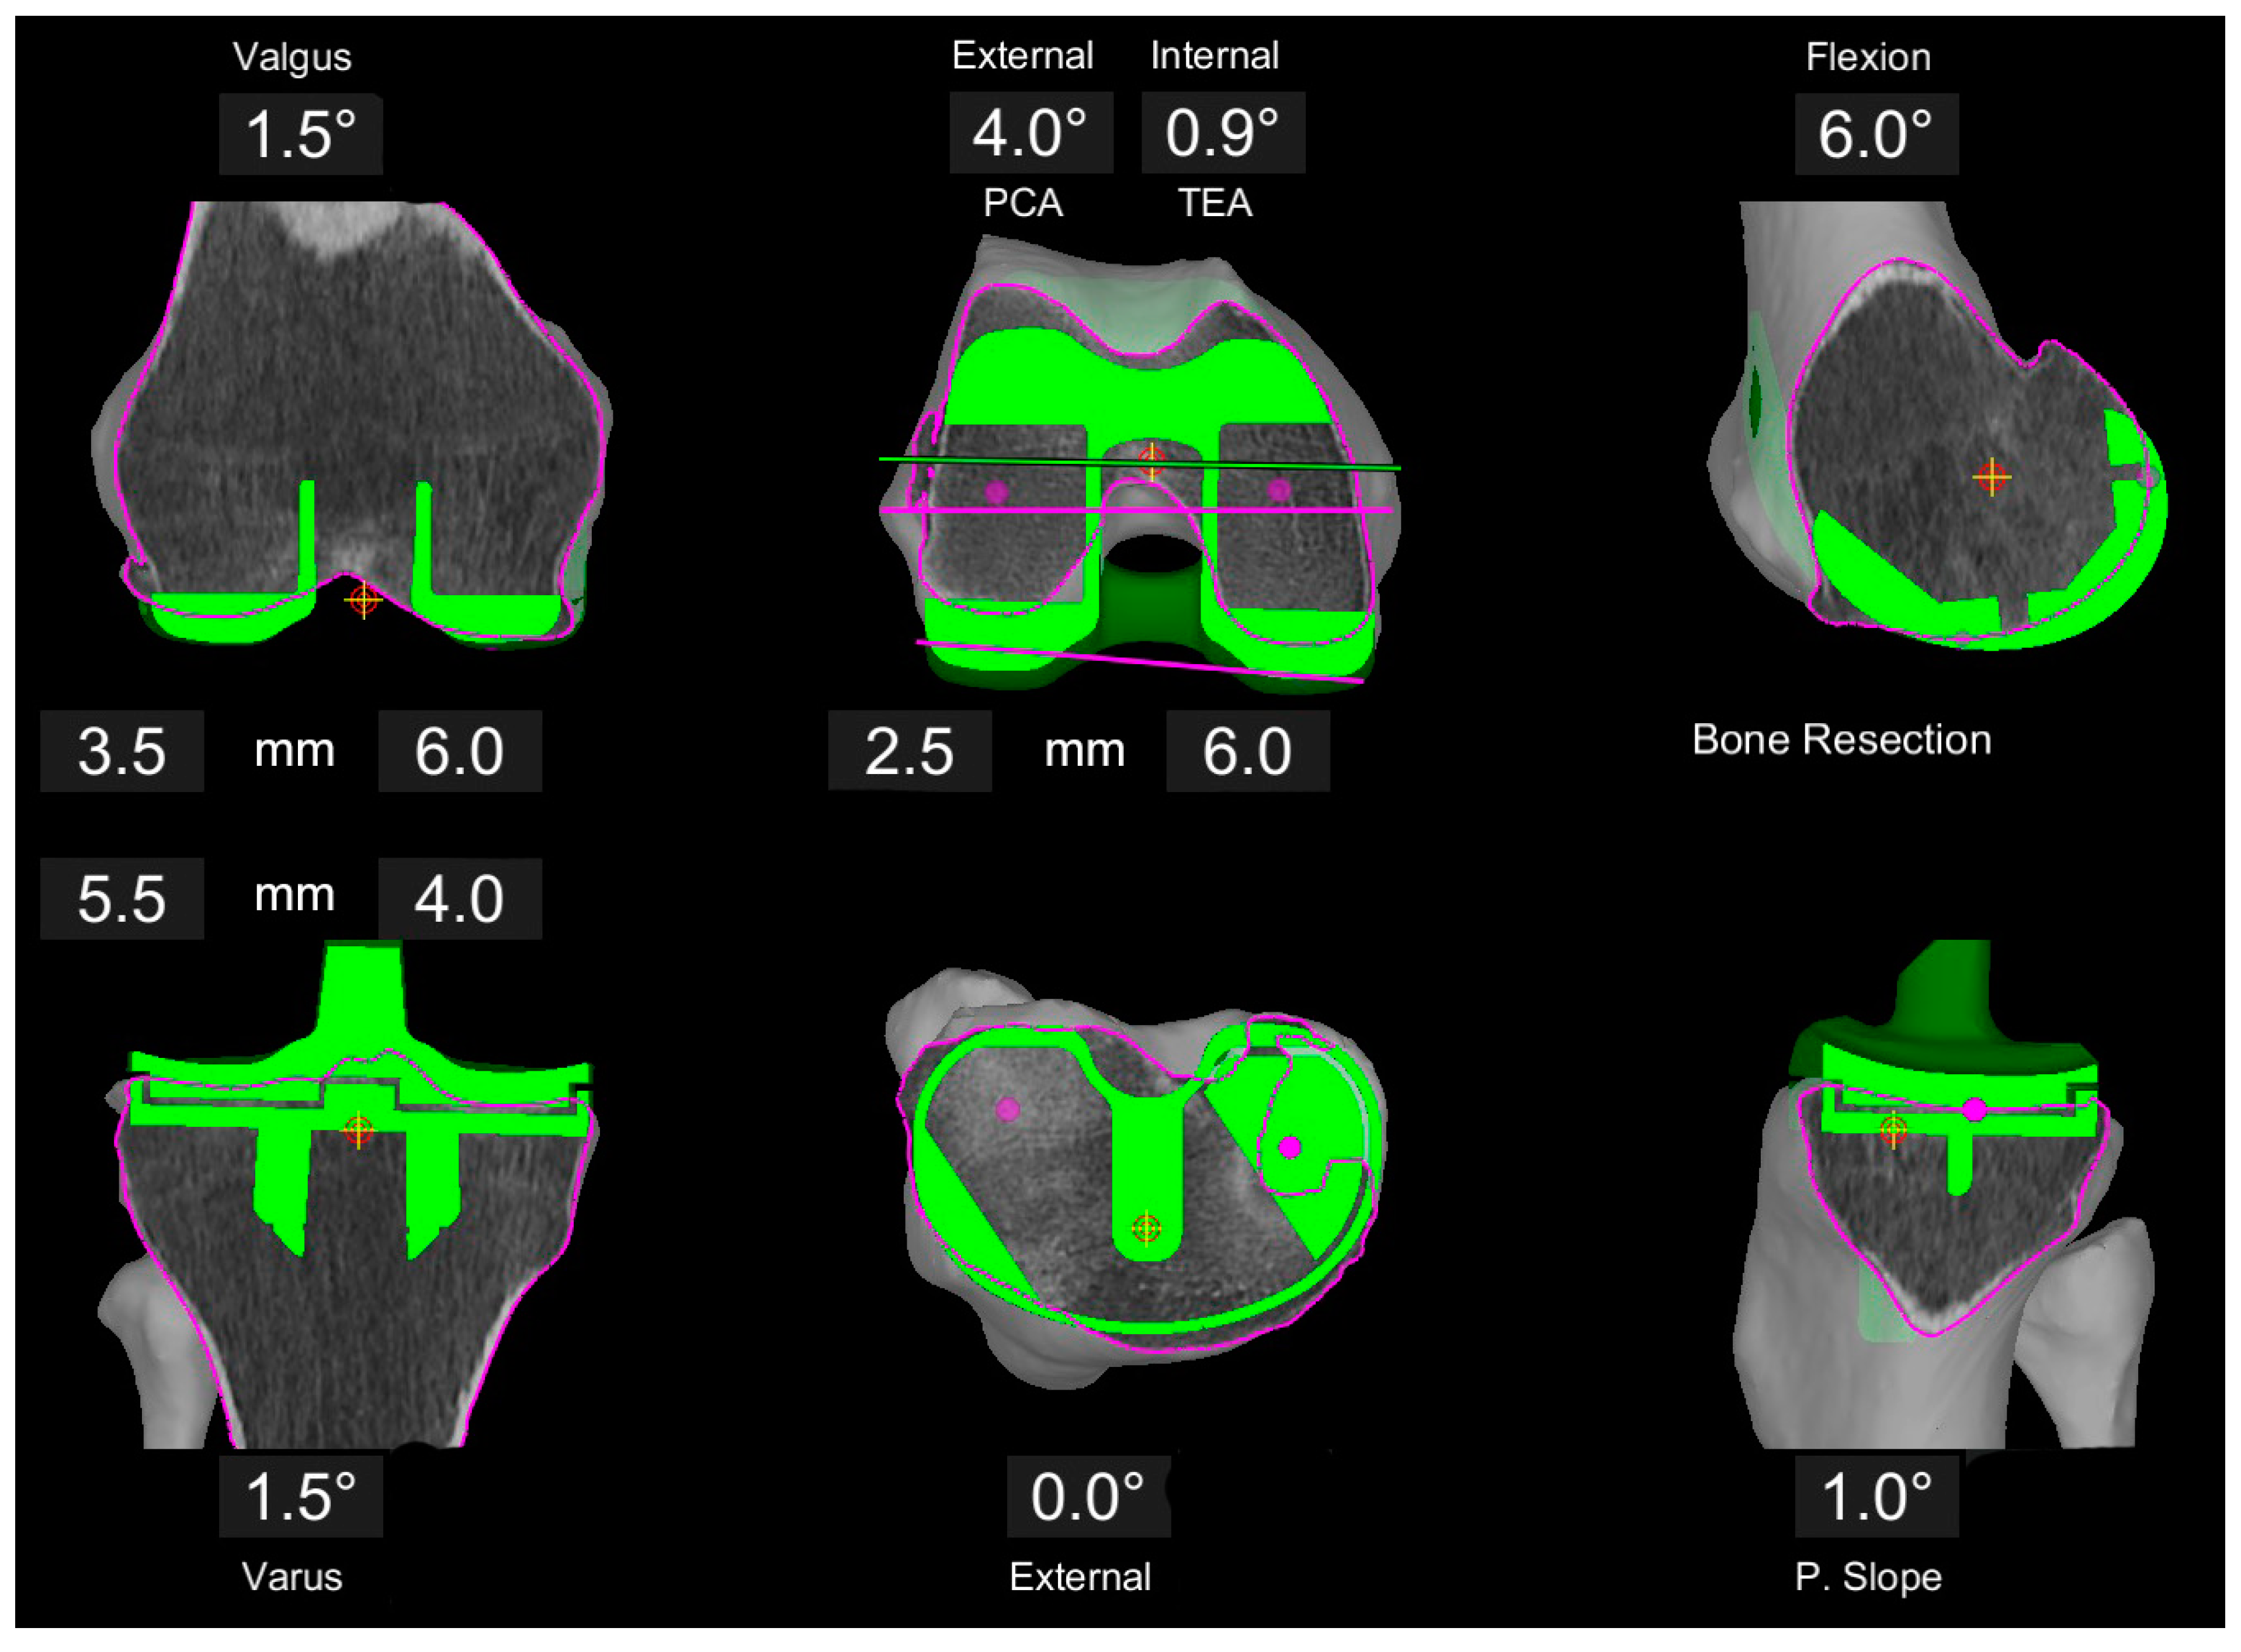

Figure 3.

Example of image-based planning of the component position based on the principles of rKA in a valgus patient. Medial femoral resections are set to 6 mm each, whereas the lateral resections are adjusted. With the tibia in 1.5° varus, a 1.5° valgus on the femur is set to create a neutral overall limb alignment in the coronal plane. Femoral rotation is set to best reconstruct the trochlea axis with the component trochlea groove resulting in 4° external rotation to the PCA (0.9° internal to TEA).